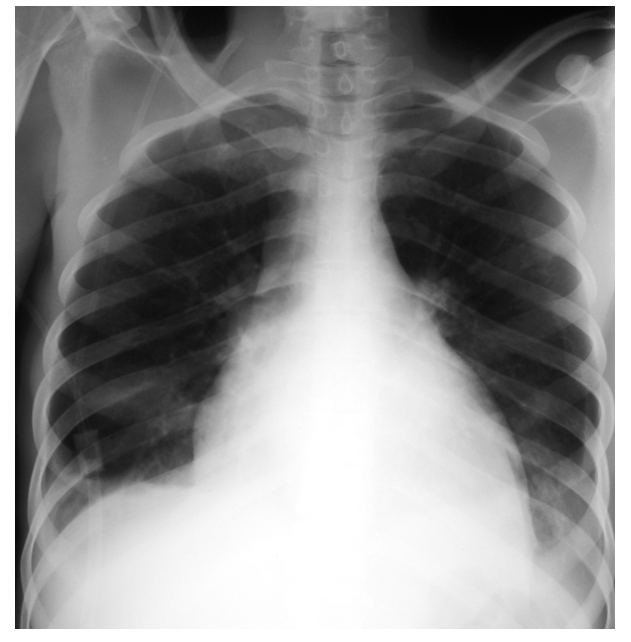

What is shown? What does it suggest in the context of pericarditis?